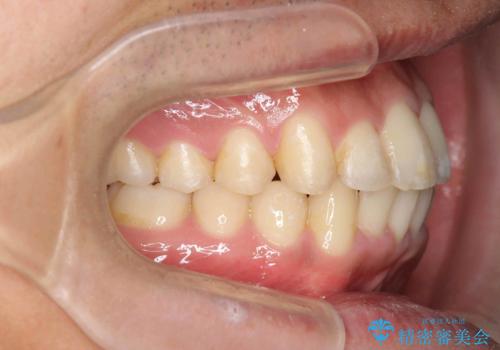

歯を抜かない矯正 奥歯のすれ違い咬合 下の八重歯

- 前歯のガタガタを主訴に来院。

奥歯はすれ違ってしまっていました。

口元も出ておらず、非抜歯を希望されたため、IPR(歯を削る処置)でスペースを確保しました。

上顎両側7番(一番奥の歯)はすれ違っており、虫歯になっていました。